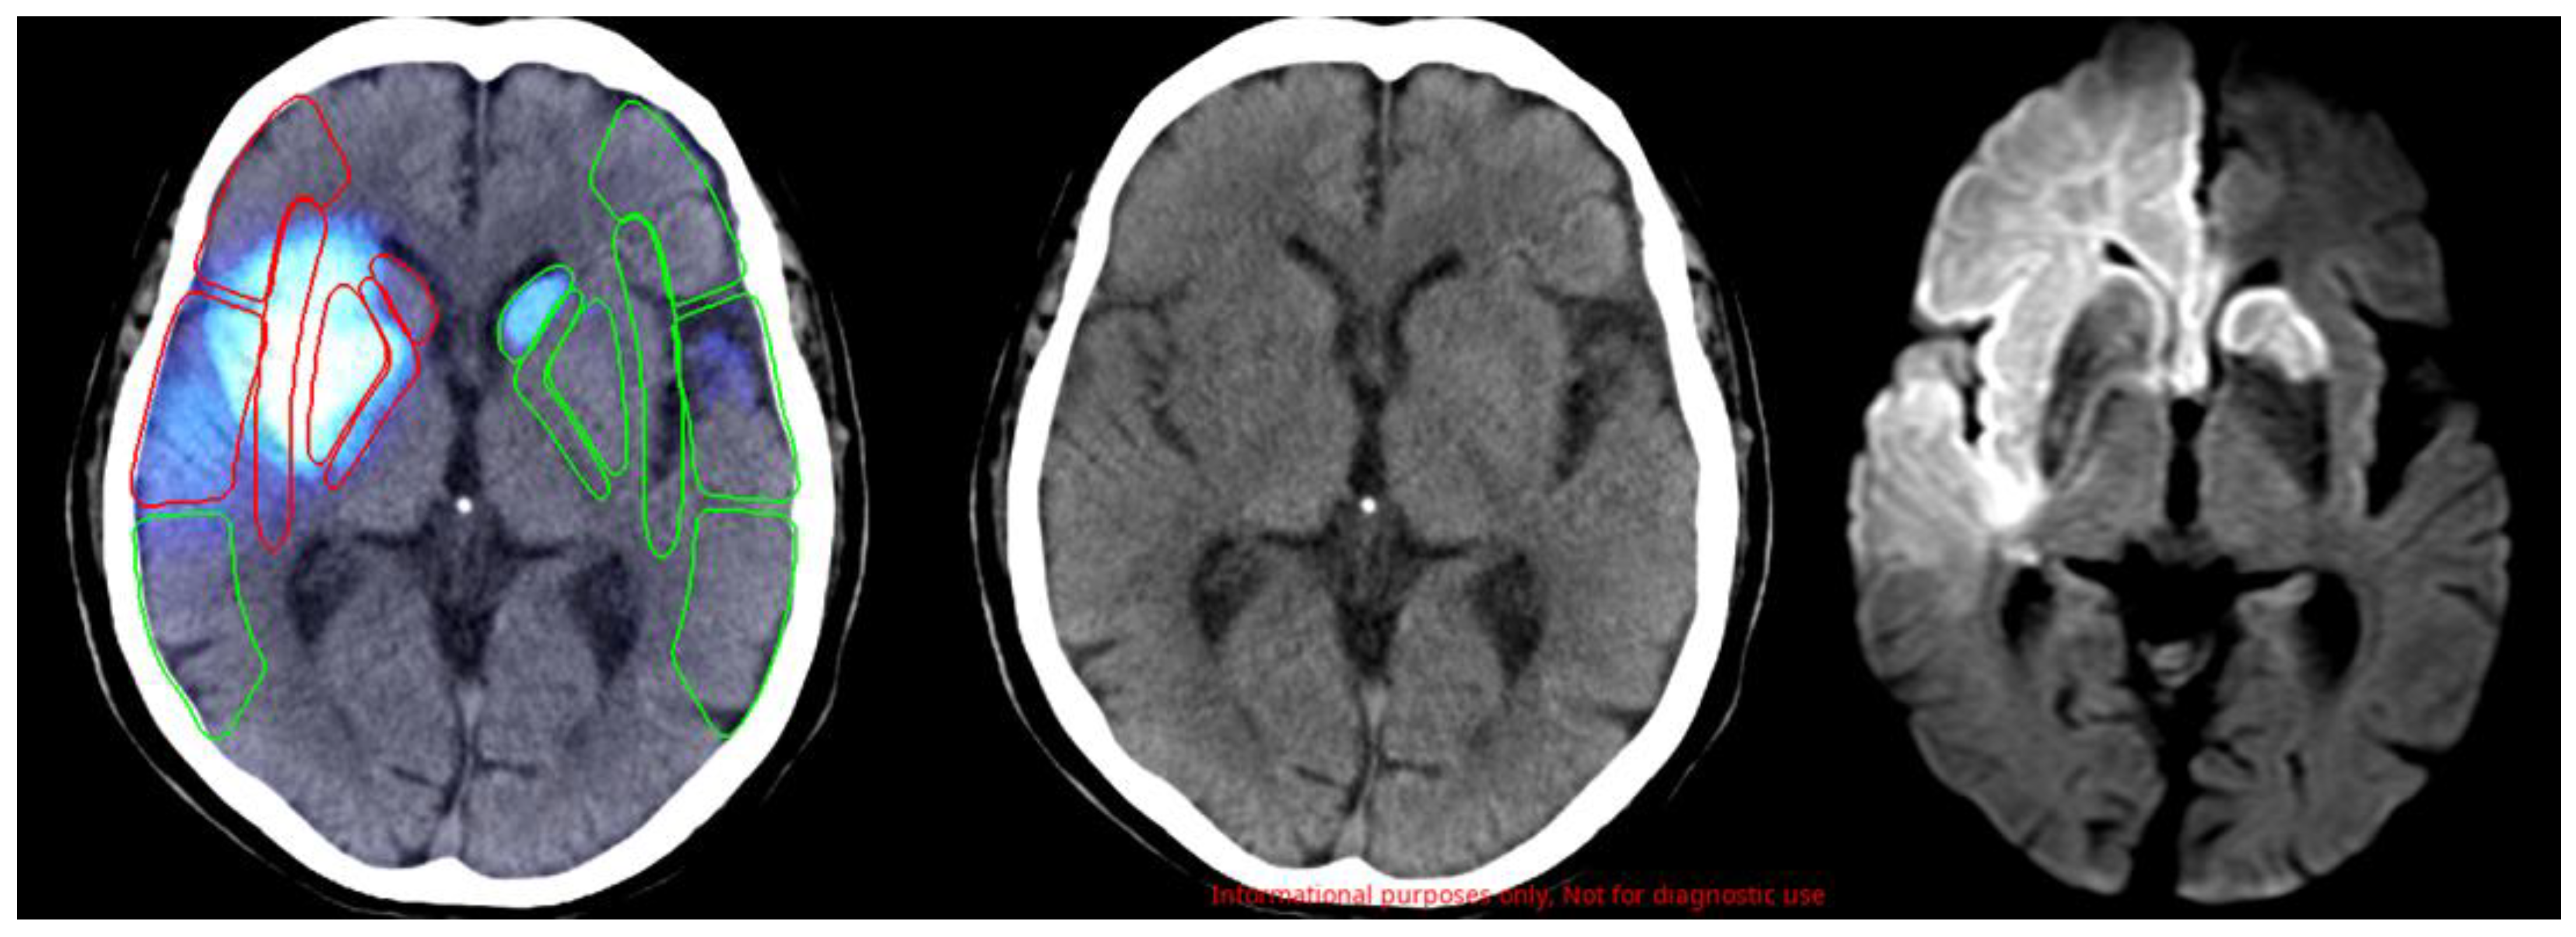

4.1. Characteristics of the AI Software